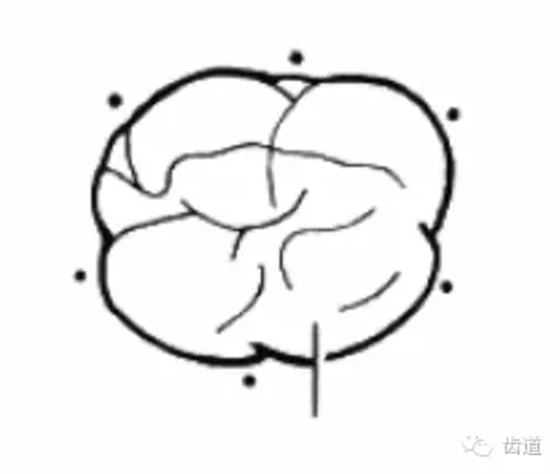

根分叉病變

工具:彎探針(Nabers探針),頂端為鈍頭,有刻度,(可用彎尖探針代替)

方法:下頜磨牙,頰舌側中央探查;上頜磨牙,頰側中央及腭側近遠中探查

內(nèi)容:

分度:Glickman分度標準

Furcation

Furcation involvement